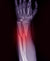

Osteoporosis is diagnosed by performing a bone mineral density test—X-ray imaging that measures the levels of calcium and other minerals in the bones of the spine, hip, and sometimes the forearm. Patients may also have a CT scan or an ultrasound.